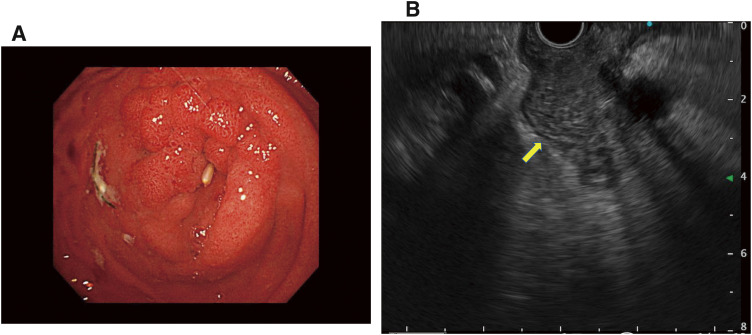

Case presentation: A 53-year-old man was admitted with abdominal distension and recurrent vomiting. Esophagogastroduodenoscopy revealed a complete duodenal obstruction without malignant findings. Computed tomography revealed wall thickening in the second portion of the duodenum. The common bile duct and main pancreatic duct were not dilated. As there was no evidence of malignancy, we performed gastrojejunostomy as a bypass to improve the symptoms. Five months later, follow-up blood examinations showed elevated total bilirubin levels, and computed tomography revealed persistent thickening of the duodenal wall with exacerbated dilation of common bile duct and main pancreatic duct. Mucosal biopsies from the oral and anal sides of the stenosis revealed no malignancy. Due to a strong suspicion of malignant disease and difficulty in preoperative biliary drainage, we performed pancreatoduodenectomy. Pathological examination revealed mucinous adenocarcinoma with submucosal and subserosal invasion of the duodenum. We finally diagnosed this case as ampullary carcinoma.